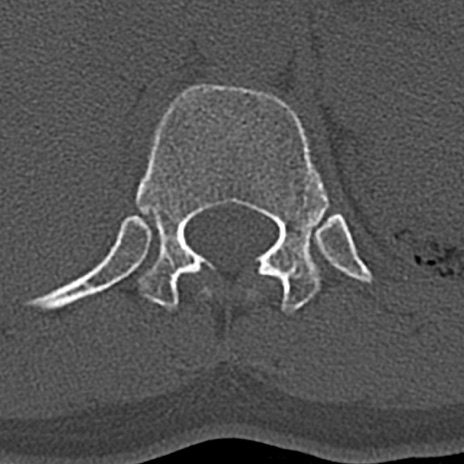

腰椎CT

横断像と矢状断像